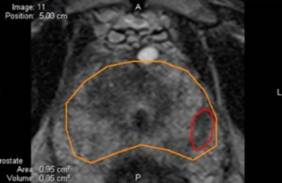

Esta nueva técnica, que requiere de una tecnología específica, combina en tiempo real la resonancia magnética de próstata multiparamétrica (RMmp) con la ecografía, de forma que se obtienen para biopsia los tejidos realmente sospechosos de corresponder a tumores clínicamente significativos que sin tratamiento pueden comprometer el pronóstico vital del paciente y son subsidiarios de intervención.

"La resonancia magnética de próstata multiparamétrica combina diferentes secuencias anatómicas y funcionales permitiendo identificar por imagen aquellas zonas con riesgo elevado de ser tumores con significación clínica", explica el doctor Miguel Sánchez Encinas, jefe del Servicio de Urología del HURJC.

"Fusionando en tiempo real las imágenes de este tipo de resonancia, se consigue aumentar la precisión diagnóstica llegando a una sensibilidad del 92%, superior a la obtenida con ecografía convencional y que obtenemos mientras el paciente está en el quirófano. Además nos permite una precisión diagnóstica mucho más elevada dado que se puede descartar la presencia de tumores prostáticos significantes casi con el 100% de seguridad, lo que sitúa al HURJC a la altura de los más prestigiosos centros internacionales que trabajan en este campo", añade el especialista.

En este contexto la técnica combinada de RMmp y ecografía, que permite al especialista estudiar a la vez diferentes secuencias anatómicas y funcionales, surge como una nueva herramienta para identificar los tejidos de la próstata que conllevan un riesgo elevado de ser tumores con significación clínica con potencial letal para el paciente.